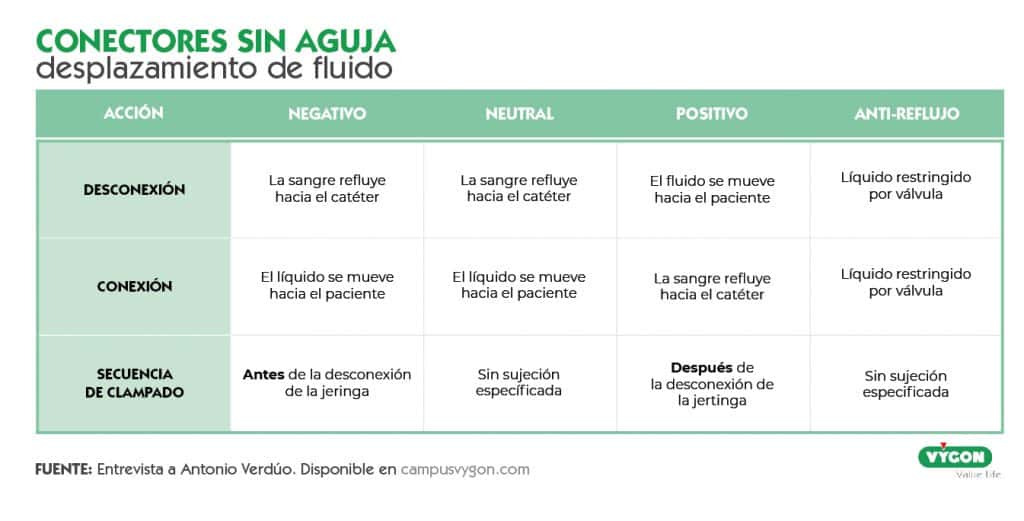

- Válvulas antirreflujo: Se trata de una válvula de control del fluido bidireccional, la cual permanece cerrada hasta que la fuerza de infusión o extracción alcanza una presión especifica y, a medida que la presión de infusión o extracción empieza a reducirse, la válvula vuelve a cerrarse. Consiguen eliminar problemas de obstrucción hasta en un 93,6% de los casos.

- Otras causas son el reflujo de sangre causado por la tos, el cambio de la presión intratorácica y la desconexión incorrecta con dispositivos de desplazamiento negativo. 5

- Procedimiento de conexión y desconexión del Luer.

Las válvulas antirreflujo son dispositivos de desplazamiento neutro a los que se les ha añadido una válvula antirreflujo.

Se trata de una válvula de control del fluido bidireccional, la cual permanece cerrada hasta que la fuerza de infusión o extracción alcanza una presión especifica y, a medida que la presión de infusión o extracción empieza a reducirse, la válvula vuelve a cerrarse. De esta forma:

- Cuando la fuerza de infusión o extracción alcanza una presión especifica: la válvula se abre.

- Al detectar una caída de presión desde la bolsa de perfusión: la válvula se mantiene cerrada.

- Cuando se produce un aumento de la presión intratorácica: la válvula se mantiene cerrada.

- Al desconectar el Luer: la válvula se mantiene cerrada.

Actualmente, el conector antirreflujo es el único dispositivo que evita la entrada de sangre en el catéter en todas estas circunstancias. Se trata de la mejor forma de prevenir el reflujo sanguíneo y la aparición de oclusión, no obstante, es importante compararentre fabricantes ya que no todos ofrecen las mismas tasas de éxito.9